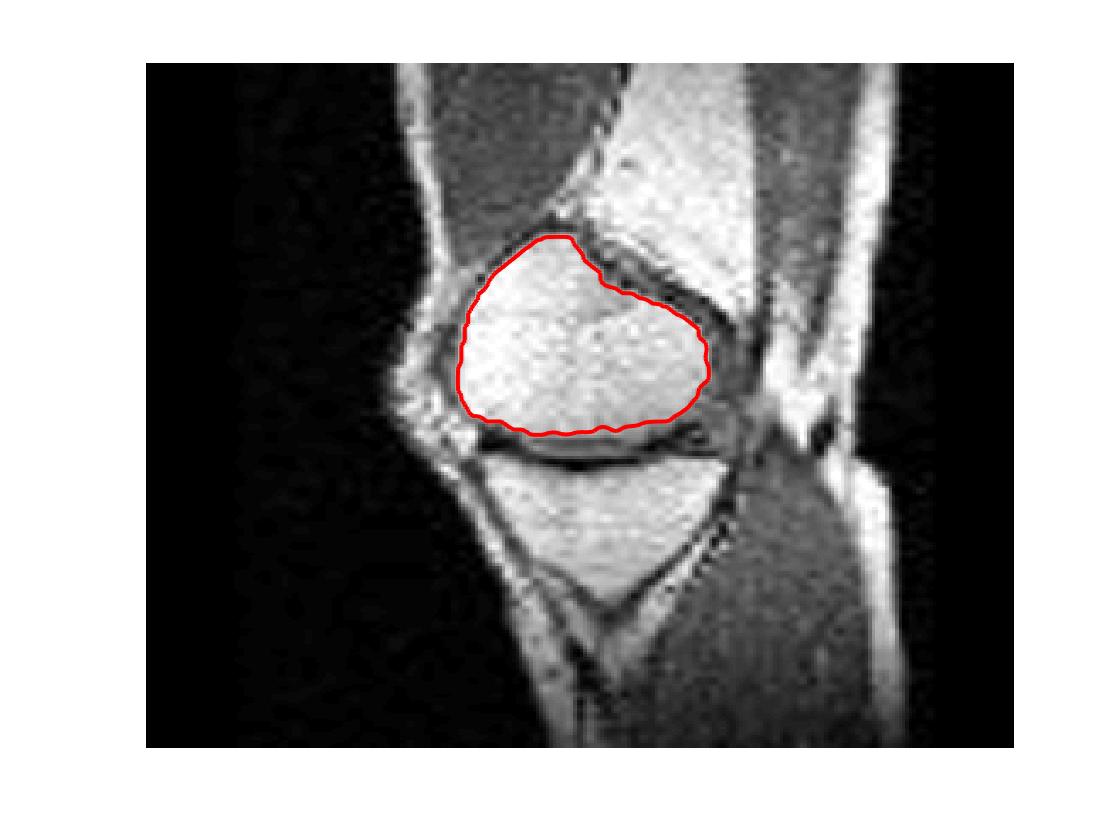

Test 2 – Test of M7’s sensitivity to changes in its main parameters. In this test we demonstrate that the proposed Geodesic Model is robust to changes in the main parameters. The main parameters in (20) are and . In all tests we set , which is simply a rescaling of the other parameters, and we set . In the first example, in Figure 12, we compare the TC value for various and values for segmentation of a bone in a knee scan. We see that the segmentation is very good for a larger range of and values. For the second example, in Figure 13, we show an image and marker set for which the Spencer-Chen model (M3) and modified Liu et al. model M6 cannot achieve the desired segmentation for any parameter range, but which can be attained for the Geodesic Model for a vast range of parameters. The final example, in Table 1, compares the TC values for various values with fixed parameters and . We use the images and ground truth as shown in Figures 12 and 13: on the synthetic circles image we obtain a perfect segmentation for all values of tested, and in the case of the knee segmentation the results are almost identical for any , above which the quality slowly deteriorates.

| Knee Segmentation (Figure 12) | Circle Segmentation (Figure 13) | |

|---|---|---|

| 0.97287 | 1.00000 | |

| 0.97235 | 1.00000 | |

| 0.96562 | 1.00000 | |

| 0.94463 | 1.00000 | |

| 0.90660 | 1.00000 | |

| 0.89573 | 1.00000 | |

| 0.89159 | 1.00000 |